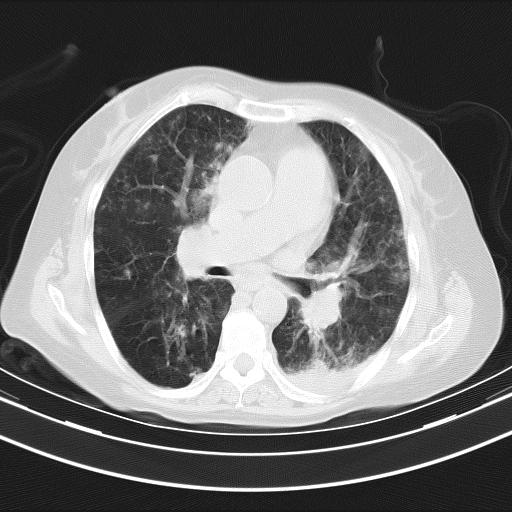

老年女性,嗜睡3天,意识模糊。轻咳,无发热。

双肺多发淡片影,毛玻璃影,,支持支气管肺炎,,建议血气找原因,,嗜睡是否肺性脑病?有没有慢支病史?

双肺炎症,建议抗炎治疗后复查,见过几个老年肺炎病例,没有发烧、咳嗽症状,直接以昏迷就诊。

1)两肺感染性病变;建议抗炎治疗后复查。2)纵隔淋巴结肿大。3)左侧胸腔积液。

1)先考虑两肺感染性病变;建议抗炎治疗后复查。

2)纵隔淋巴结肿大。

3)左侧胸腔积液。